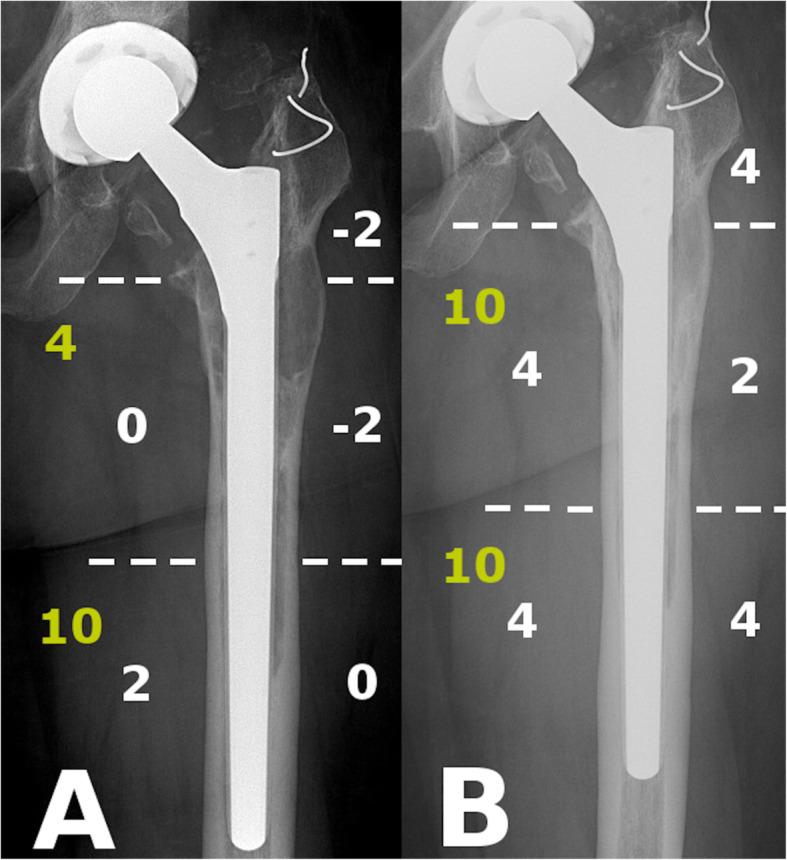

Consecutive patients between January 2015 and December 2017 undergoing femoral revision using the Wagner SL stem for PFF or AL without an extended trochanteric osteotomy (ETO) or bone grafting were selected from our database. Radiological follow-up was performed using plain antero-posterior hip radiographs taken postoperatively and at 3, 6, 12 months and at 24 months. The Global Radiological Score (GRxS) was utilized by four blinded observers. Intra and interobserver variability was calculated. Secondary outcome measures included the Oxford Hip Score and the Visual Analog Scale for pain.

We identified 20 patients from our database, 10 PFF and 10 AL cases. The severity of AL was Paprosky 2 in 2 cases, Paprosky 3A in 2 cases and Paprosky 3B in 6. PFF were classified as Vancouver B2 in 7 cases and Vancouver B3 in 3 cases. Patients undergoing femoral revision for PFF regained 89% (GRxS: 17.7/20) of their bone stock by 6 months, whilst patients with AL, required almost 2 years to achieve similar reconstitution of proximal femoral bony architecture 86% (GRxS: 17.1/20). Inter-observer reproducibility for numerical GRxS values showed a "good" correlation with 0.68, whilst the intra-observer agreement was "very good" with 0.89. Except immediate after the revision, we found a significant difference between the GRxS results of the two groups at each timepoint with pair-wise comparisons. Functional results were similar in the two groups. We were not able to show a correlation between GRxS and functional results.

我们从数据库中确定了20例患者,其中10例PFF和10例AL。AL的严重程度为2例Paprosky 2型,2例Paprosky 3A型和6例Paprosky 3B型。PFF中7例为温哥华B2型,3例为温哥华B3型。接受PFF股骨翻修的患者在6个月时恢复了89%(GRxS:17.7/20)的骨量,而AL患者则需要近2年时间才能实现股骨近端骨结构的类似重建,为86%(GRxS:17.1/20)。GRxS数值的观察者间再现性显示“良好”相关性,为0.68,而观察者内一致性为“非常好”,为0.89。除翻修后即刻外,两组GRxS结果在每个时间点的两两比较中均存在显著差异。两组的功能结果相似。我们未能显示GRxS与功能结果之间的相关性。